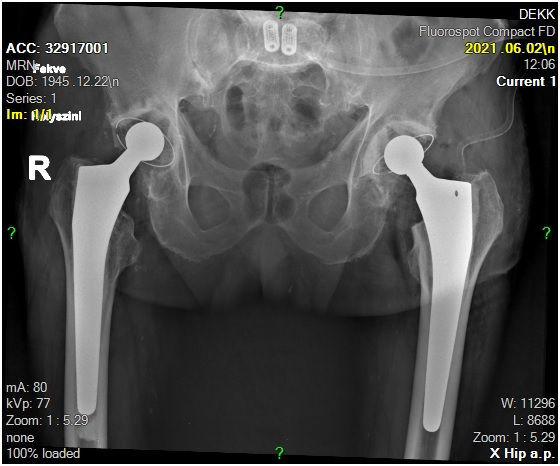

29 éves pályám során közel ezer térdprotézist és több mint kétezer csípőprotézist ültettem be. Az utóbbi években egyre több, nagy műszer igényű, összetett protézis revíziós műtétet végzek.

Fő érdeklődési köröm a biomechanika, műszerfejlesztés, új műtéti technikák kidolgozása és a nagyízületi endoprotetika.